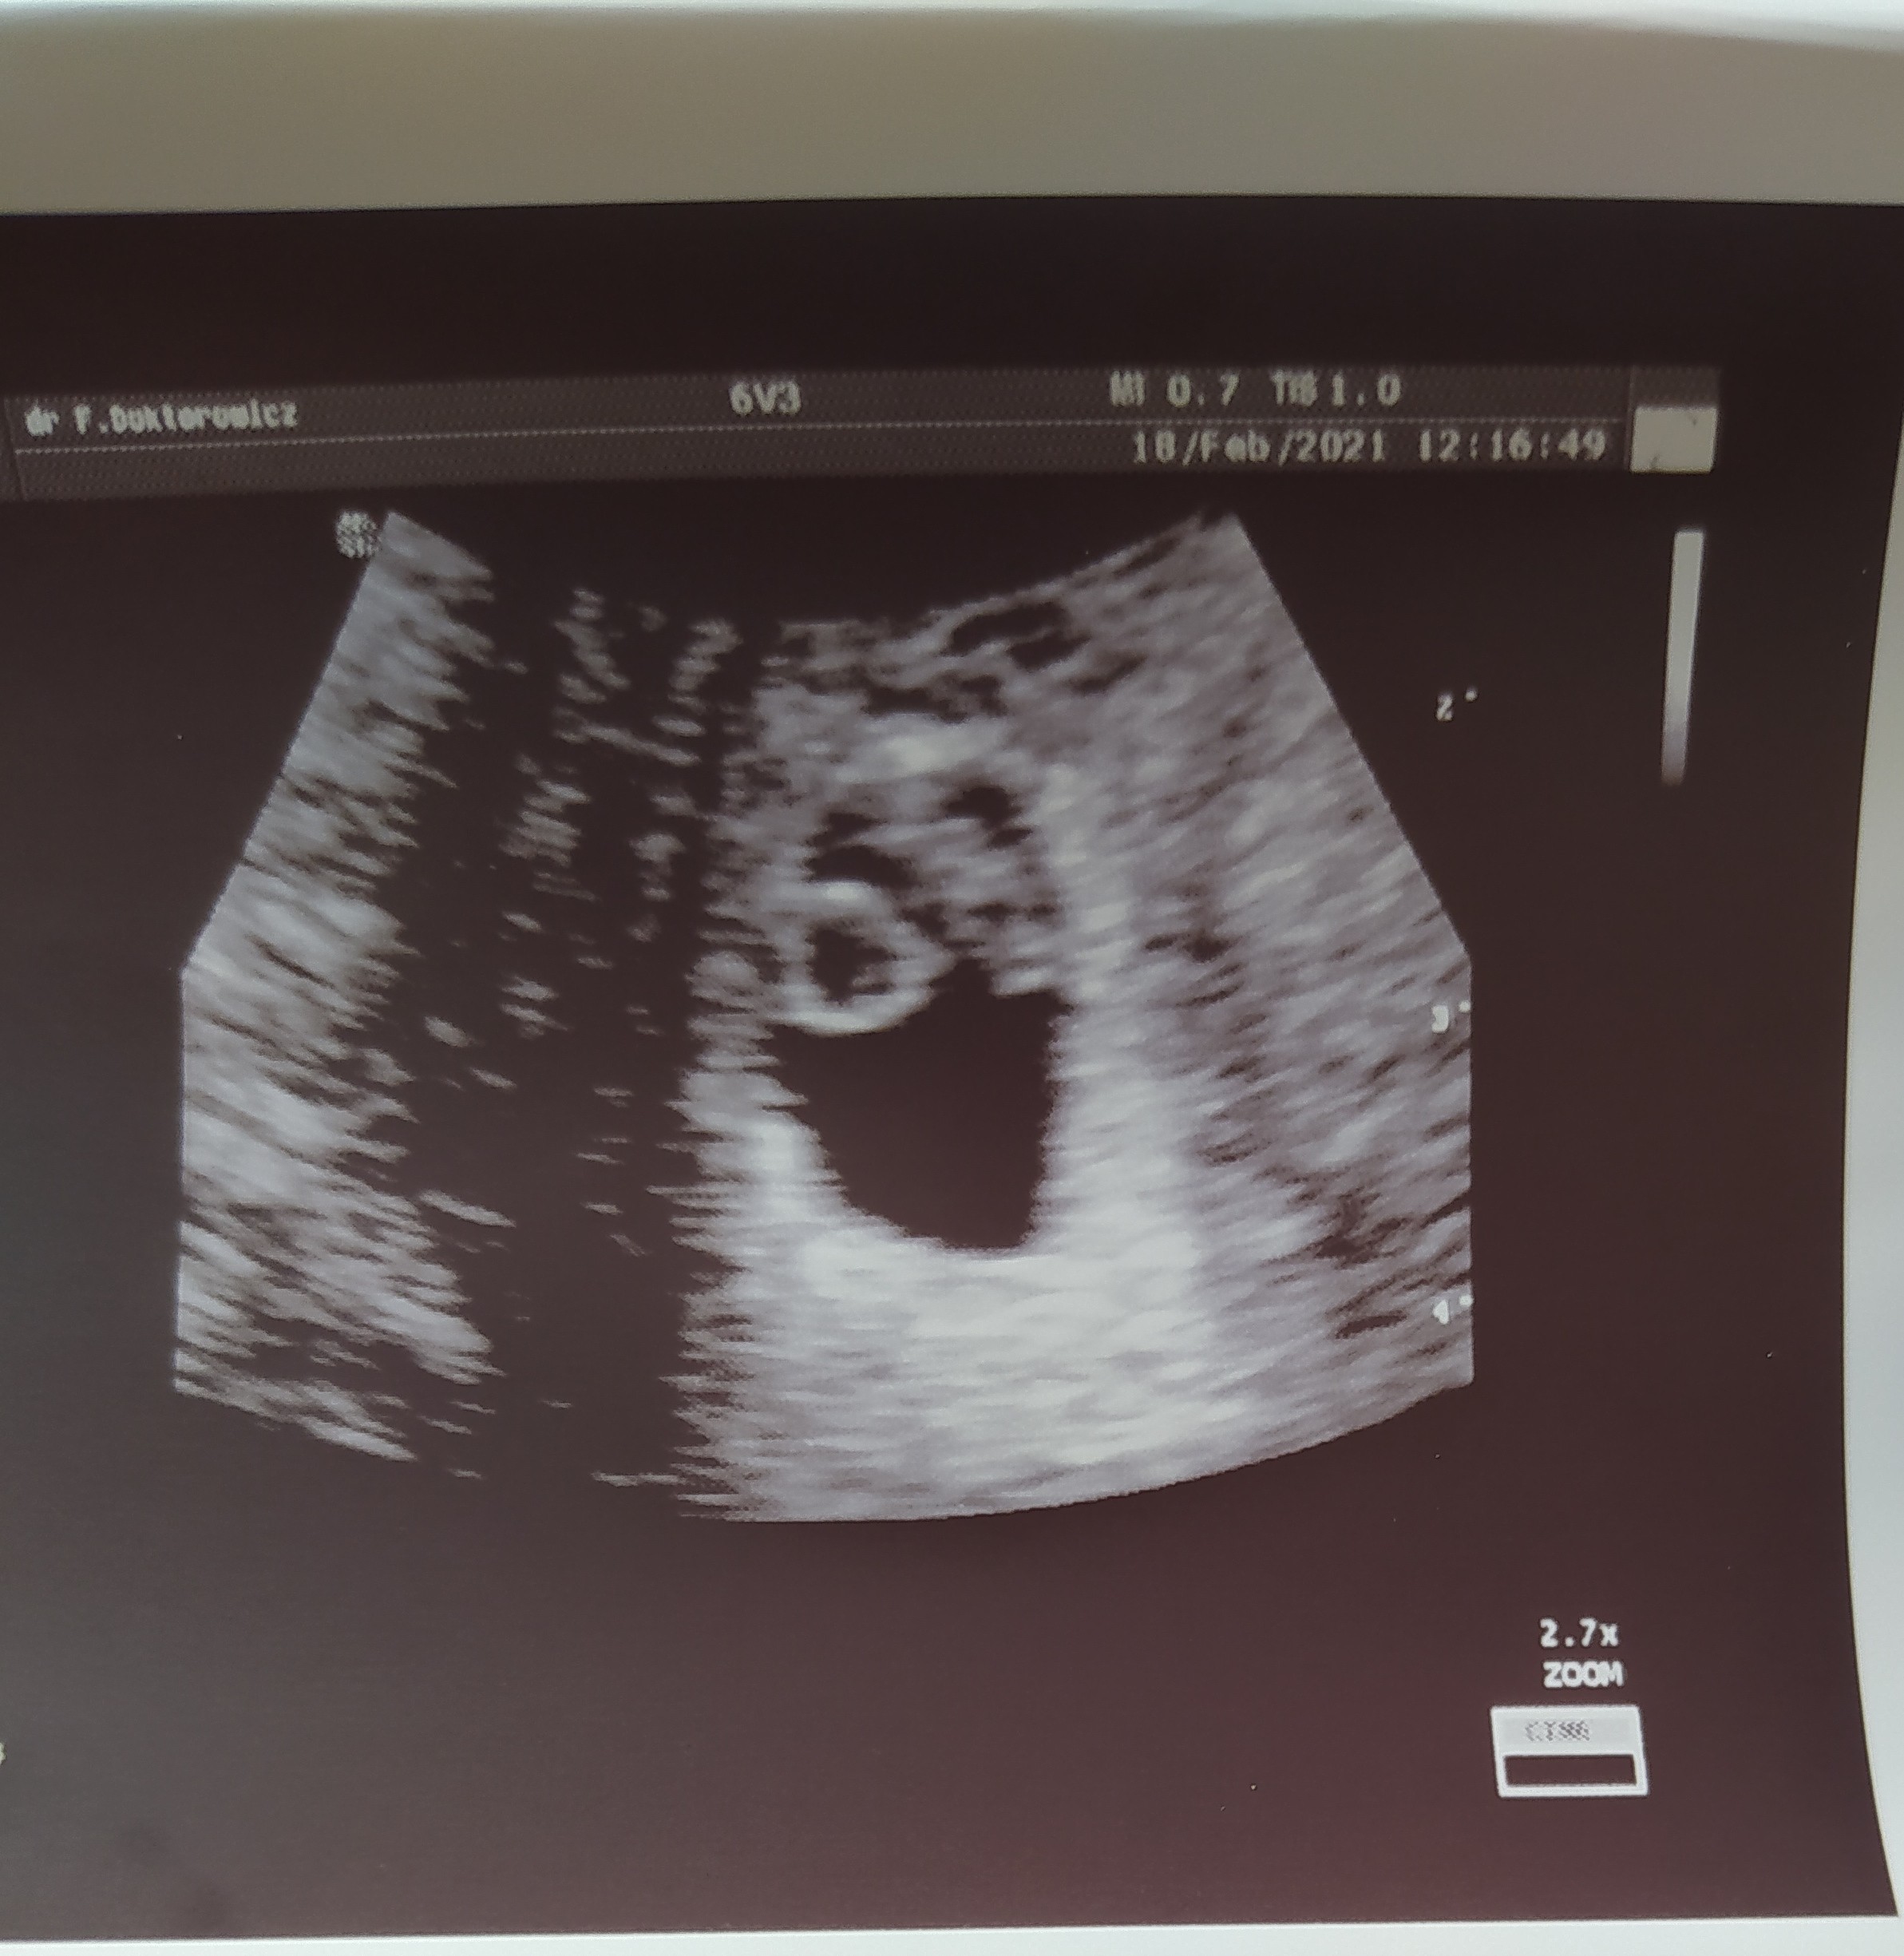

Dzień dobry, ja także dziś już po kolejnej wizycie tym razem u mojego Filipka prywatnie, serduszka nadal nie słuchałam ale nie będę narzekać, najważniejsze, że bije jak dzwon 🔔😍 mamy już 8.3mm 😊

Załączniki

• IMG_20210218_140818.jpg

IMG_20210218_140818.jpg

730,4 KB · Wyświetleń: 87

Zastanawiam się w którym tygodniu iść, ponieważ w pierwszej ciąży w 7 tyg miałam już takie usg. I nie wiem czy jakbym poszła teraz w 6 tyg czy też by było tak widoczne